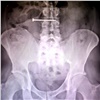

Красноярец случайно проглотил пятисантиметровый саморез, пока обшивал дом сайдингом Красноярец случайно проглотил пятисантиметровый саморез, пока обшивал дом сайдингом 6

Красноярец случайно проглотил саморез и сам обратился в краевую больницу.